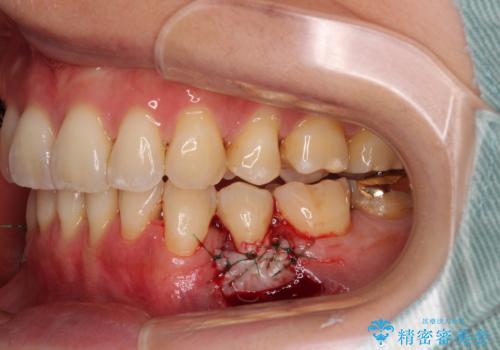

口蓋(上顎の内側)から採取した結合組織(歯肉の内側の組織)を移植することによる、根面被覆術を行うこととしました。

移植片には、極力角化歯肉が多く残るようにし、被覆するだけでなく、歯肉の厚みを増やし、角化歯肉を回復させることができました。